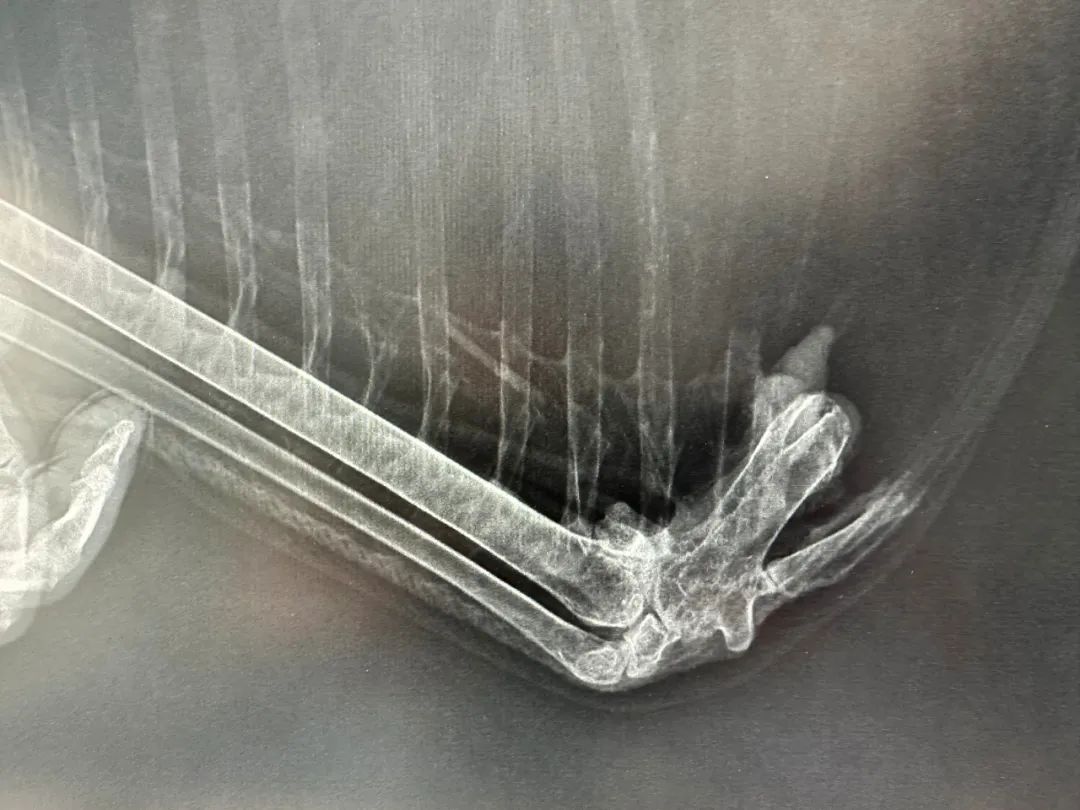

蓝天白云正是秋高气爽时,有朝一日小白可以展翅翱翔。当然,这一幕是众所期待的,汪湜决定带她去安庆骨科医院给受伤的翅膀拍张X光片,于是乎,小白的历险记也将被开启……

9时40分,目的地终于到了。小白下车后,站在医院的大厅里,她舒展了双翼,抖了抖身子,很快便用长长的喙开始梳理起羽毛来。说实话,她也挺有包袱的,很注意自己的形象。在志愿者和医护人员的共同帮助下,小白非常配合地完成了左边翅膀X光片的拍摄。院长说她受伤部位除有骨质增生外,没有发现其他异常,不太会影响她在自然状态下生活。